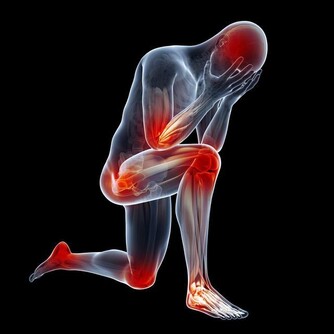

5.腿部膝眼長贅肉,說明膝關節出現問題了,一般表現為膝關節疼痛,上樓困難等。